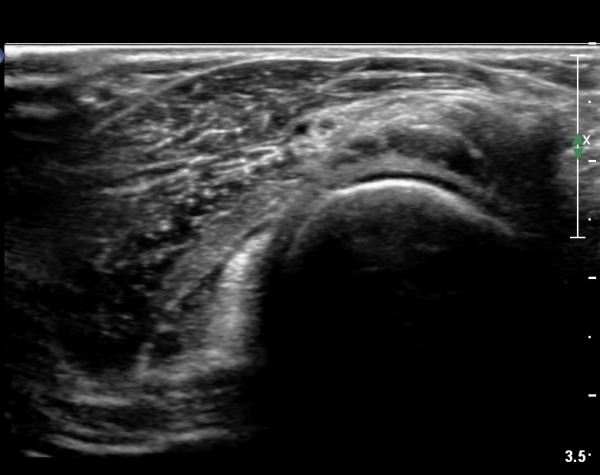

¿ä°ñµÎ ºÎÀ§ ÆÈ²ÞÄ¡ ¾Õ, ¿ÜÃø Ⱦ´Ü¸é°Ë»ç¿¡¼­ Èİñ°£ ½Å°æ ³»Ãø, ¿ä°ñµÎ Ç¥Ãþ¿¡¼­

ÀÛÀº ³¶Á¾ÀÌ °üÂûµÈ´Ù(»çÁø 3)

ŽÃÊÀÚ¸¦¸»´ÜÀ¸·Î  À̵¿ÇÏ´Ï ¿ä°ñ¸ñ ºÎÀ§¿¡¼­ Ä¿´Ù¶õ ³¶Á¾ÀÌ Èİñ°£ ½Å°æÀ» ¾Ð¹ÚÇÏ´Â °ÍÀÌ

°üÂûµÈ´Ù(»çÁø 4, 5)